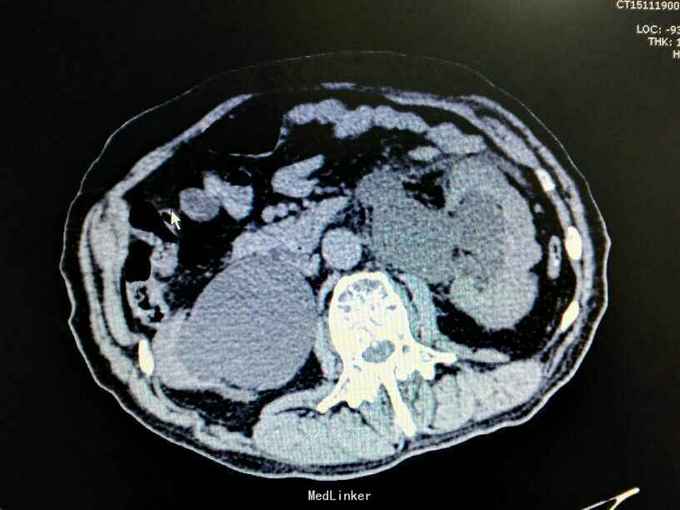

男性,87岁,进行性排尿困难10年,小便不能自解2天入院。无血尿,无发热、腰痛。一直口服藏药治疗前列腺增生症。既往无高血压、糖尿病。

腹部明显膨隆。耻骨上膀胱区扣浊。肾区无扣痛。尿常规少许白细胞。肌酐506,电解质正常。Hb116。

前列腺增生症 尿潴留 双肾积水 肾功能不全,膀胱结石,尿路感染,双肾多发囊肿。给予留置导尿,间断分次放尿后,出现肉眼血尿,持续膀胱冲洗,颜色较红,伴血凝块间断堵管。